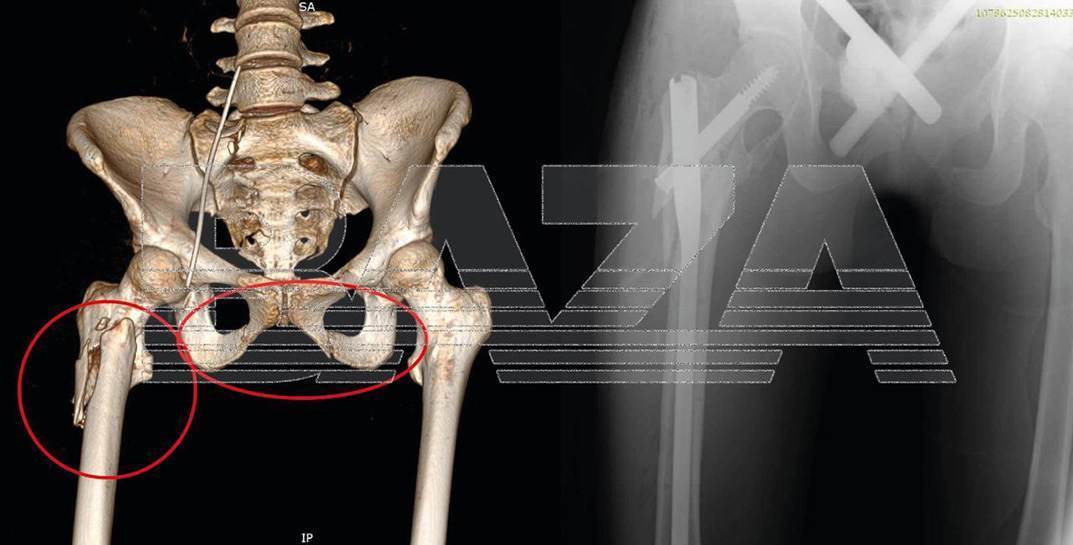

Молодая россиянка была сильно «поломана»: черепно-мозговая травма, закрытое повреждение грудной клетки с поражением легких, а также переломы костей таза и бедра, травма живота.

Пострадавшей сразу начали массивное переливание крови, ввели антибиотики, дренировали лёгкие и наложили аппараты внешней фиксации на переломы. На пятые сутки девушка пришла в сознание, врачи стабилизировал ее состояние и через две недели уже выписали из больницы.